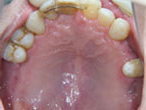

初診時

上下顎に数本の歯が残っていますが咬合支持がほとんどないために満足に食事もできない状態でした。また、下顎前歯部から臼歯部にかけて骨吸収が進行しており、上顎臼歯部にインプラント治療を行うためには骨造成が必要な状態です。

上顎